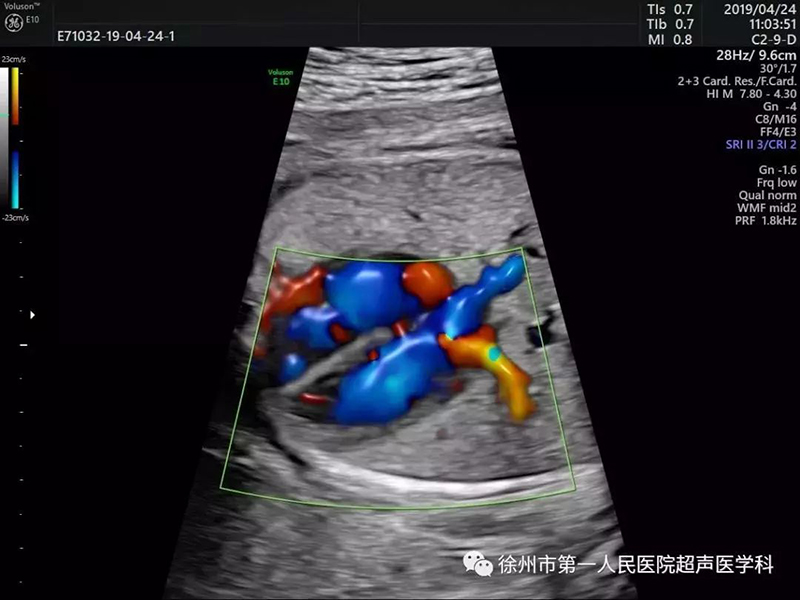

心臟超聲檢測(cè)更立體 評(píng)估更確切

心臟超聲檢測(cè)對(duì)于超聲圖像質(zhì)量及輔助的診斷工具要求非常高。美國(guó)GE Voluson E10優(yōu)異的圖像分辨率,能在四維空間內(nèi)展現(xiàn)立體的心臟結(jié)構(gòu)和功能,能更精準(zhǔn)檢查胎兒心臟發(fā)育情況。

E10具備一整套卓越的胎心成像技術(shù)(STIC),支持從胎兒心臟結(jié)構(gòu)到心功能的分析,是胎兒心臟檢測(cè)評(píng)估領(lǐng)域的技術(shù)領(lǐng)導(dǎo)。雙平面成像技術(shù)可真實(shí)呈現(xiàn)胎心結(jié)構(gòu)、臍帶、血流變化,幫助臨床醫(yī)生及時(shí)作出確切診斷,是目前超聲領(lǐng)域診斷的利器。